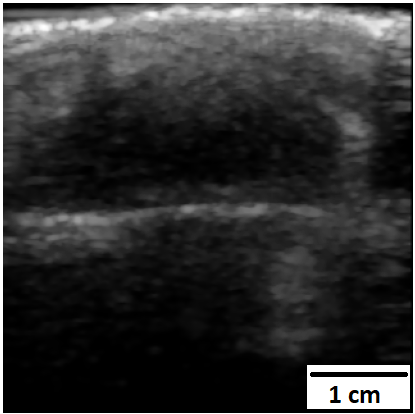

Chronic wounds including diabetic and arterial/venous insufficiency injuries have become a major burden for healthcare systems worldwide. Demographic changes suggest that wound care will play an even bigger role in the coming decades. Predicting and monitoring response to therapy in wound care is currently largely based on visual inspection with little information on the underlying tissue. Thus, there is an urgent unmet need for innovative approaches that facilitate personalized diagnostics and treatments at the point-of-care. It has been recently shown that ultrasound imaging can monitor response to therapy in wound care, but this work required onerous manual image annotations. In this study, we present initial results of a deep learning-based automatic segmentation of cross-sectional wound size in ultrasound images and identify requirements and challenges for future research on this application. Evaluation of the segmentation results underscores the potential of the proposed deep learning approach to complement non-invasive imaging with Dice scores of 0.34 (U-Net, FCN) and 0.27 (ResNet-U-Net) but also highlights the need for improving robustness further. We conclude that deep learning-supported analysis of non-invasive ultrasound images is a promising area of research to automatically extract cross-sectional wound size and depth information with potential value in monitoring response to therapy.